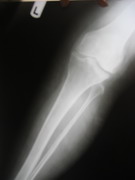

Knee Joints Case B

Knee Joint Replacement Knee Joint Replacement Knee Joint Replacement